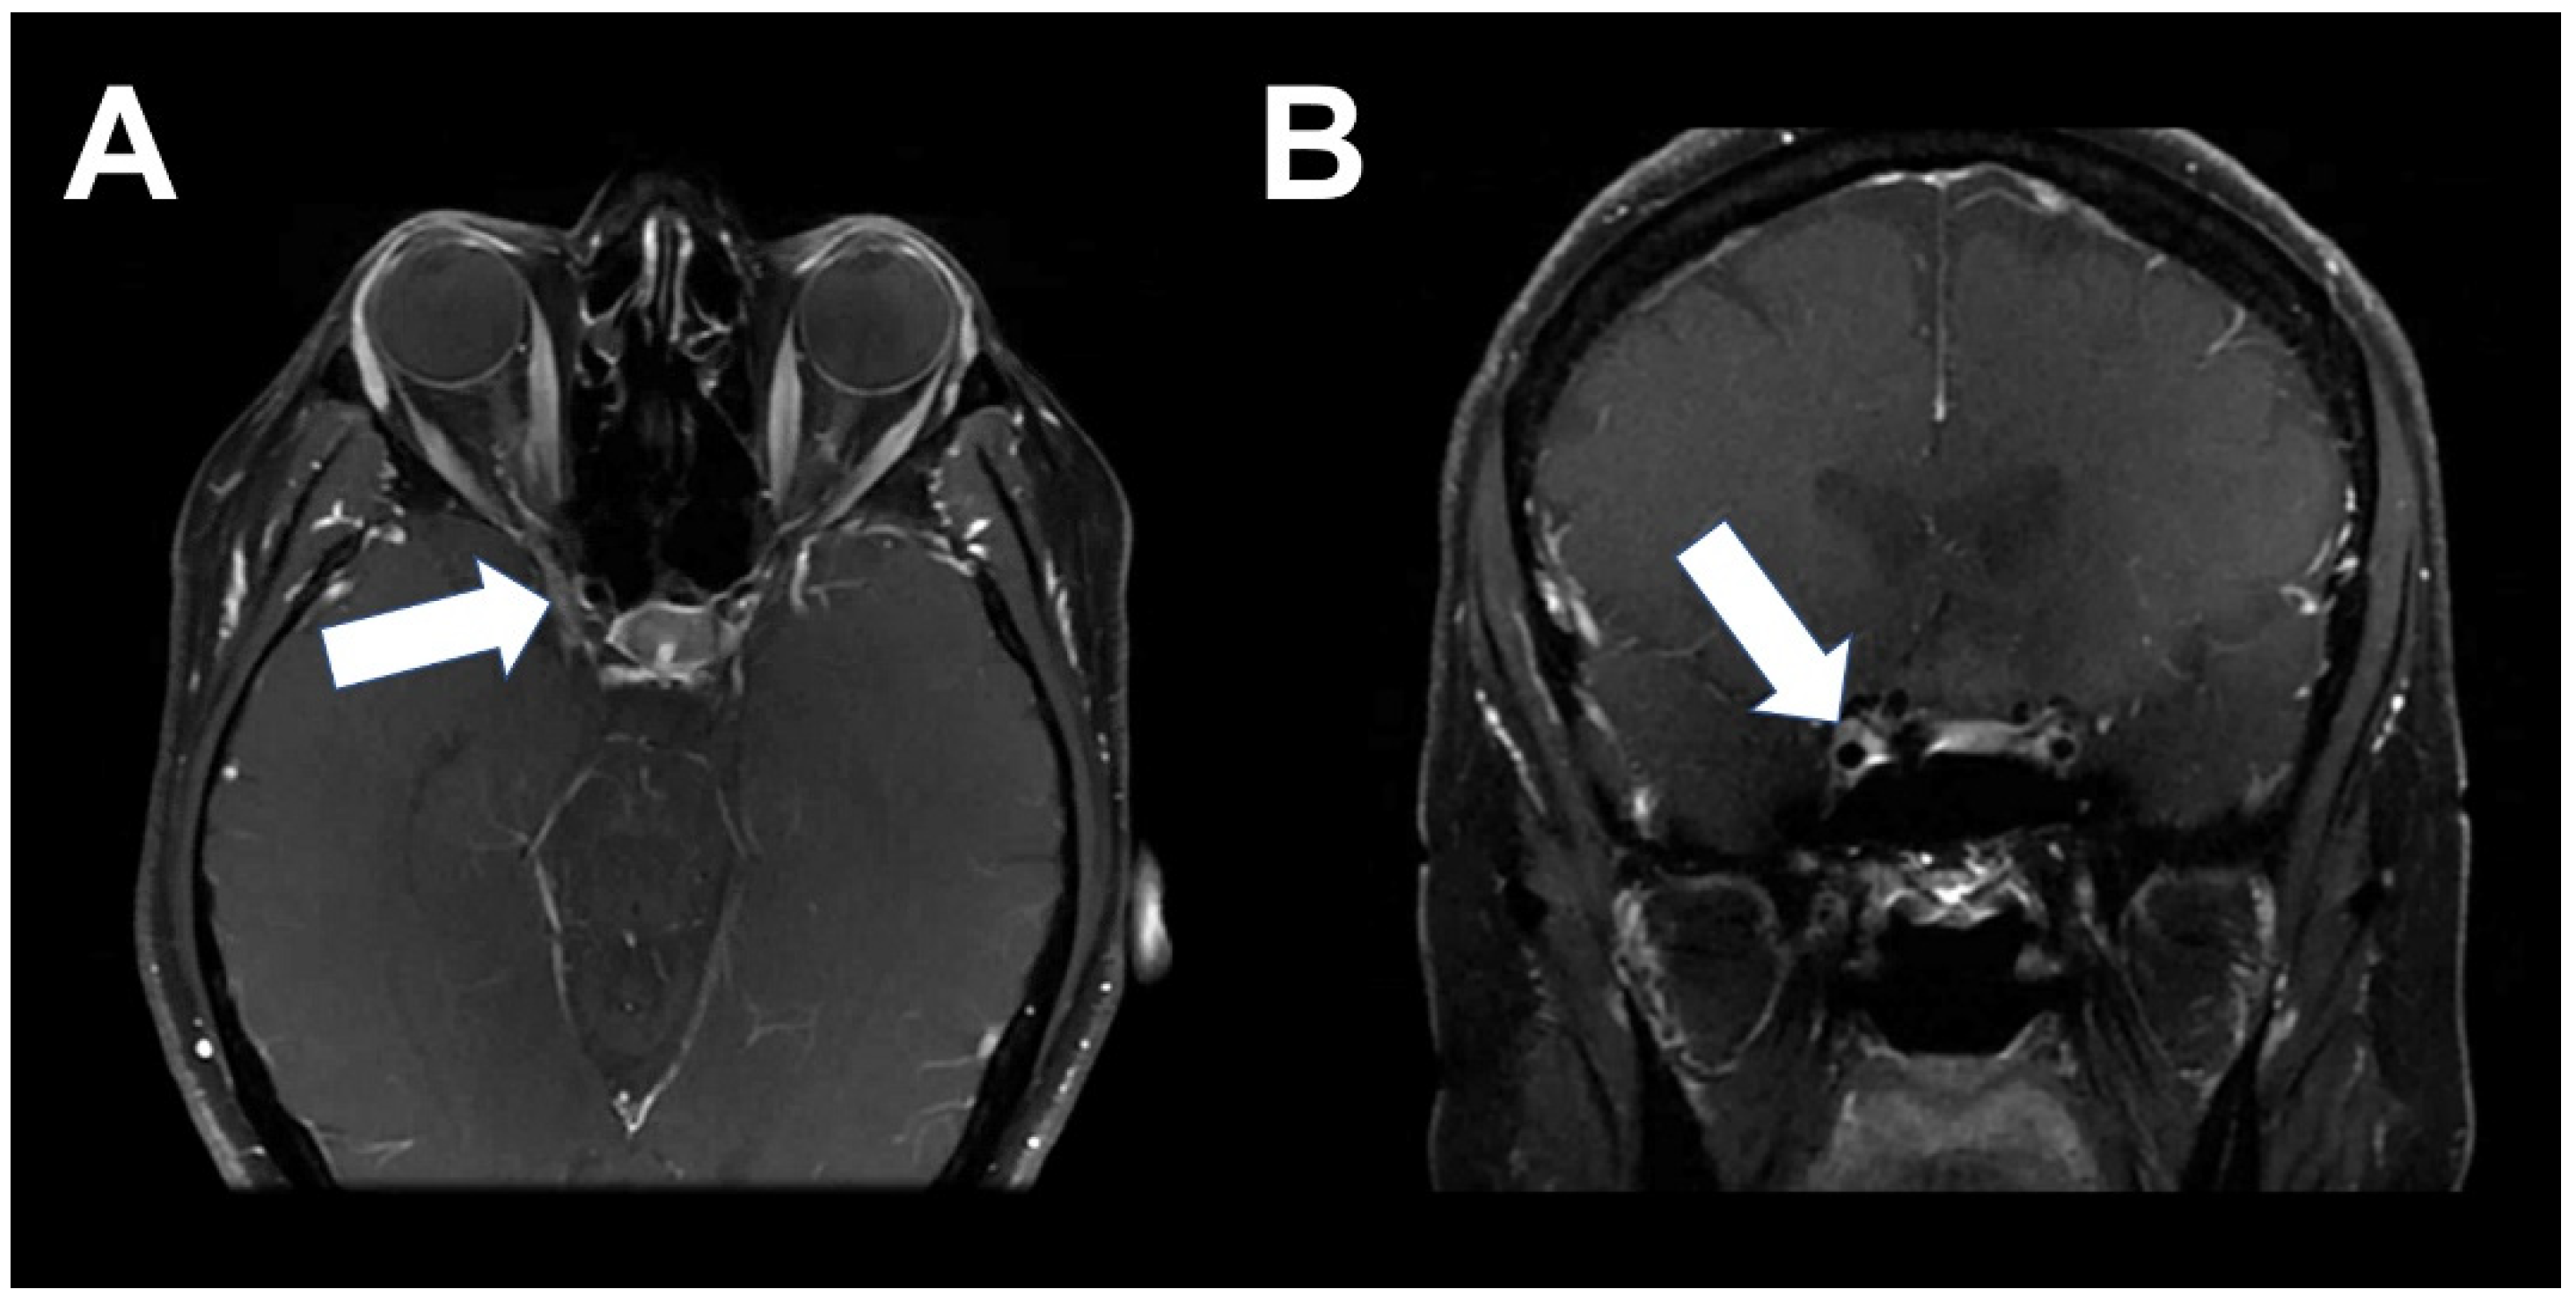

2. Case 1

3. Case 2